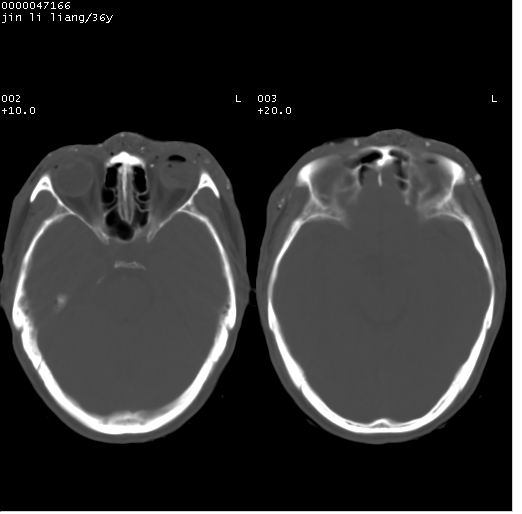

患者 男,36岁。头面部“土炮”炸伤。pe:面目全非,伤口流血不止。

临床诊断:头面部外伤。

颅脑ct轴位平扫(层厚、层距均为10mm),图像如下:

痛心,左眼啊!好在颅内还好。

1左侧眼球破裂并积气,球内、框内异物。

2额部顶部软组织伤。